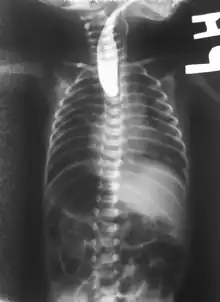

On plain X-ray, a feeding tube will not be seen pass through the esophagus and remain coiled in the upper oesophageal pouch.[8]

If any of the above signs/symptoms are noticed, a catheter is gently passed into the esophagus to check for resistance. If resistance is noted, other studies will be done to confirm the diagnosis. A catheter can be inserted and will show up as white on a regular x-ray film to demonstrate the blind pouch ending. Sometimes a small amount of barium (chalk-like liquid) is placed through the mouth to diagnose the problems.